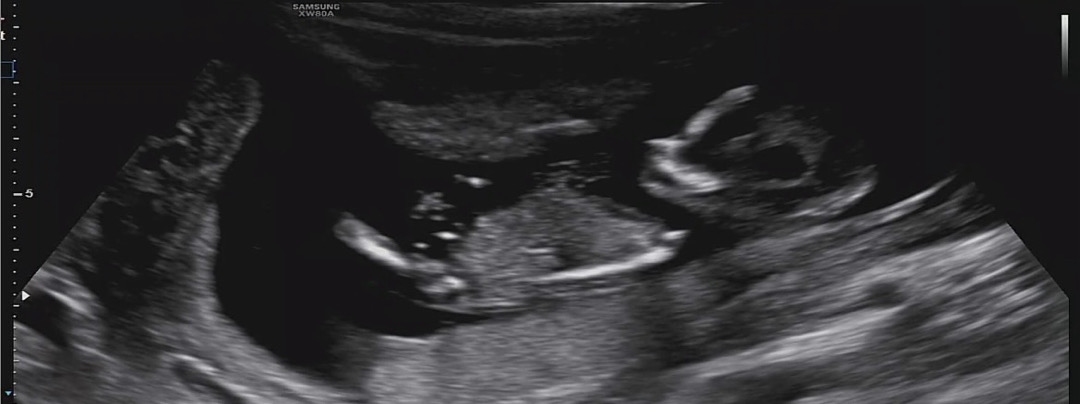

12주 2일 초음파 성별 투표 부탁드립니다~

사진 보시고 투표 한번 부탁드리니다~